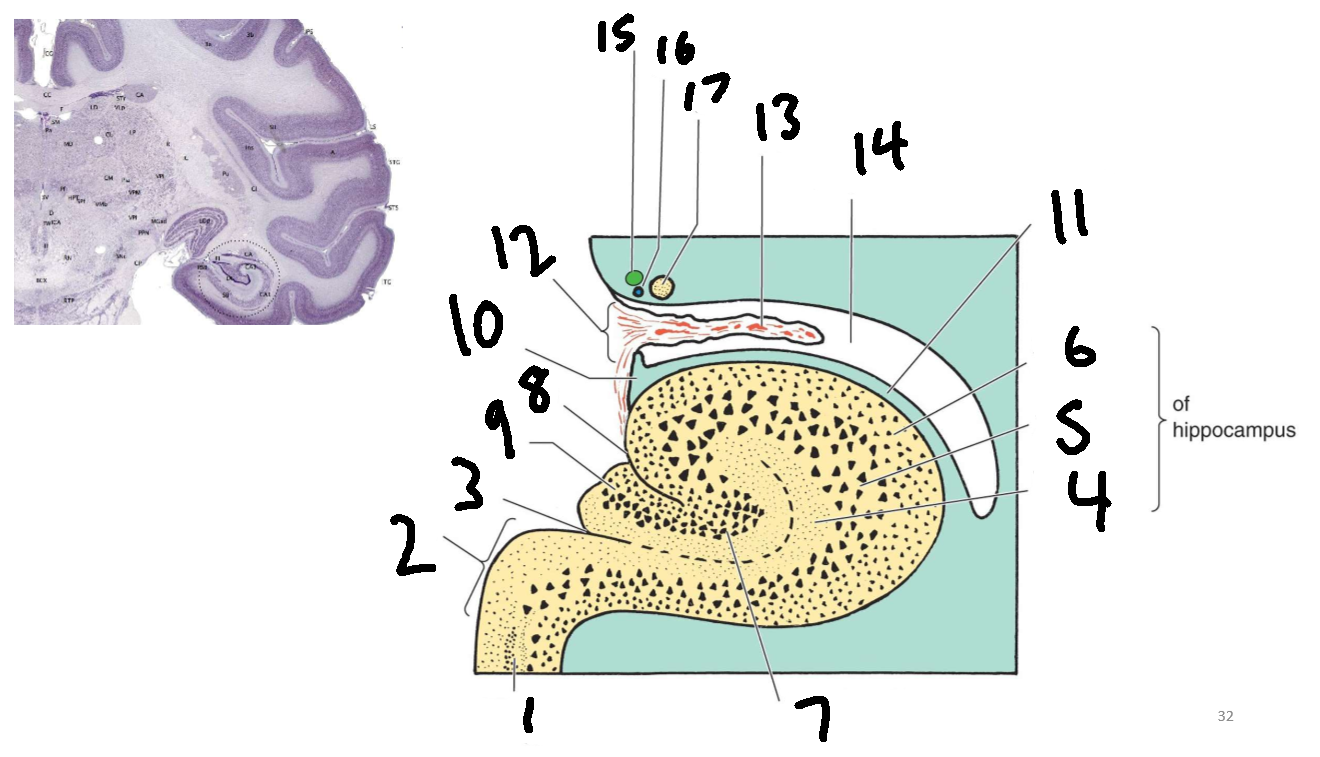

What is 1?

parahippocampal gyrus

What is 2?

subiculum

What is 3?

hippocampal sulcus

What is 4?

molecular layer

What is 5?

pyramidal layer

What is 6?

polymorphic cell layer

What is 7?

granule cell layer of dentate gyrus

What is 8?

fimbriodentate sulcus

What is 9?

dentate gyrus

What is 10?

fimbria of hippocampus

What is 11?

alveus

What is 12?

choroid fissure

What is 13?

choroid plexus

What is 14?

temporal horn of lateral ventricle

What is 15?

stria terminalis

What is 16?

thalamostriate vein

What is 17?

tail of caudate nucleus